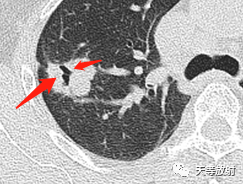

右肺上叶结节影,周围更小结节,形态不规则,胸膜面相对干净。

实性为主结节,长条状影。